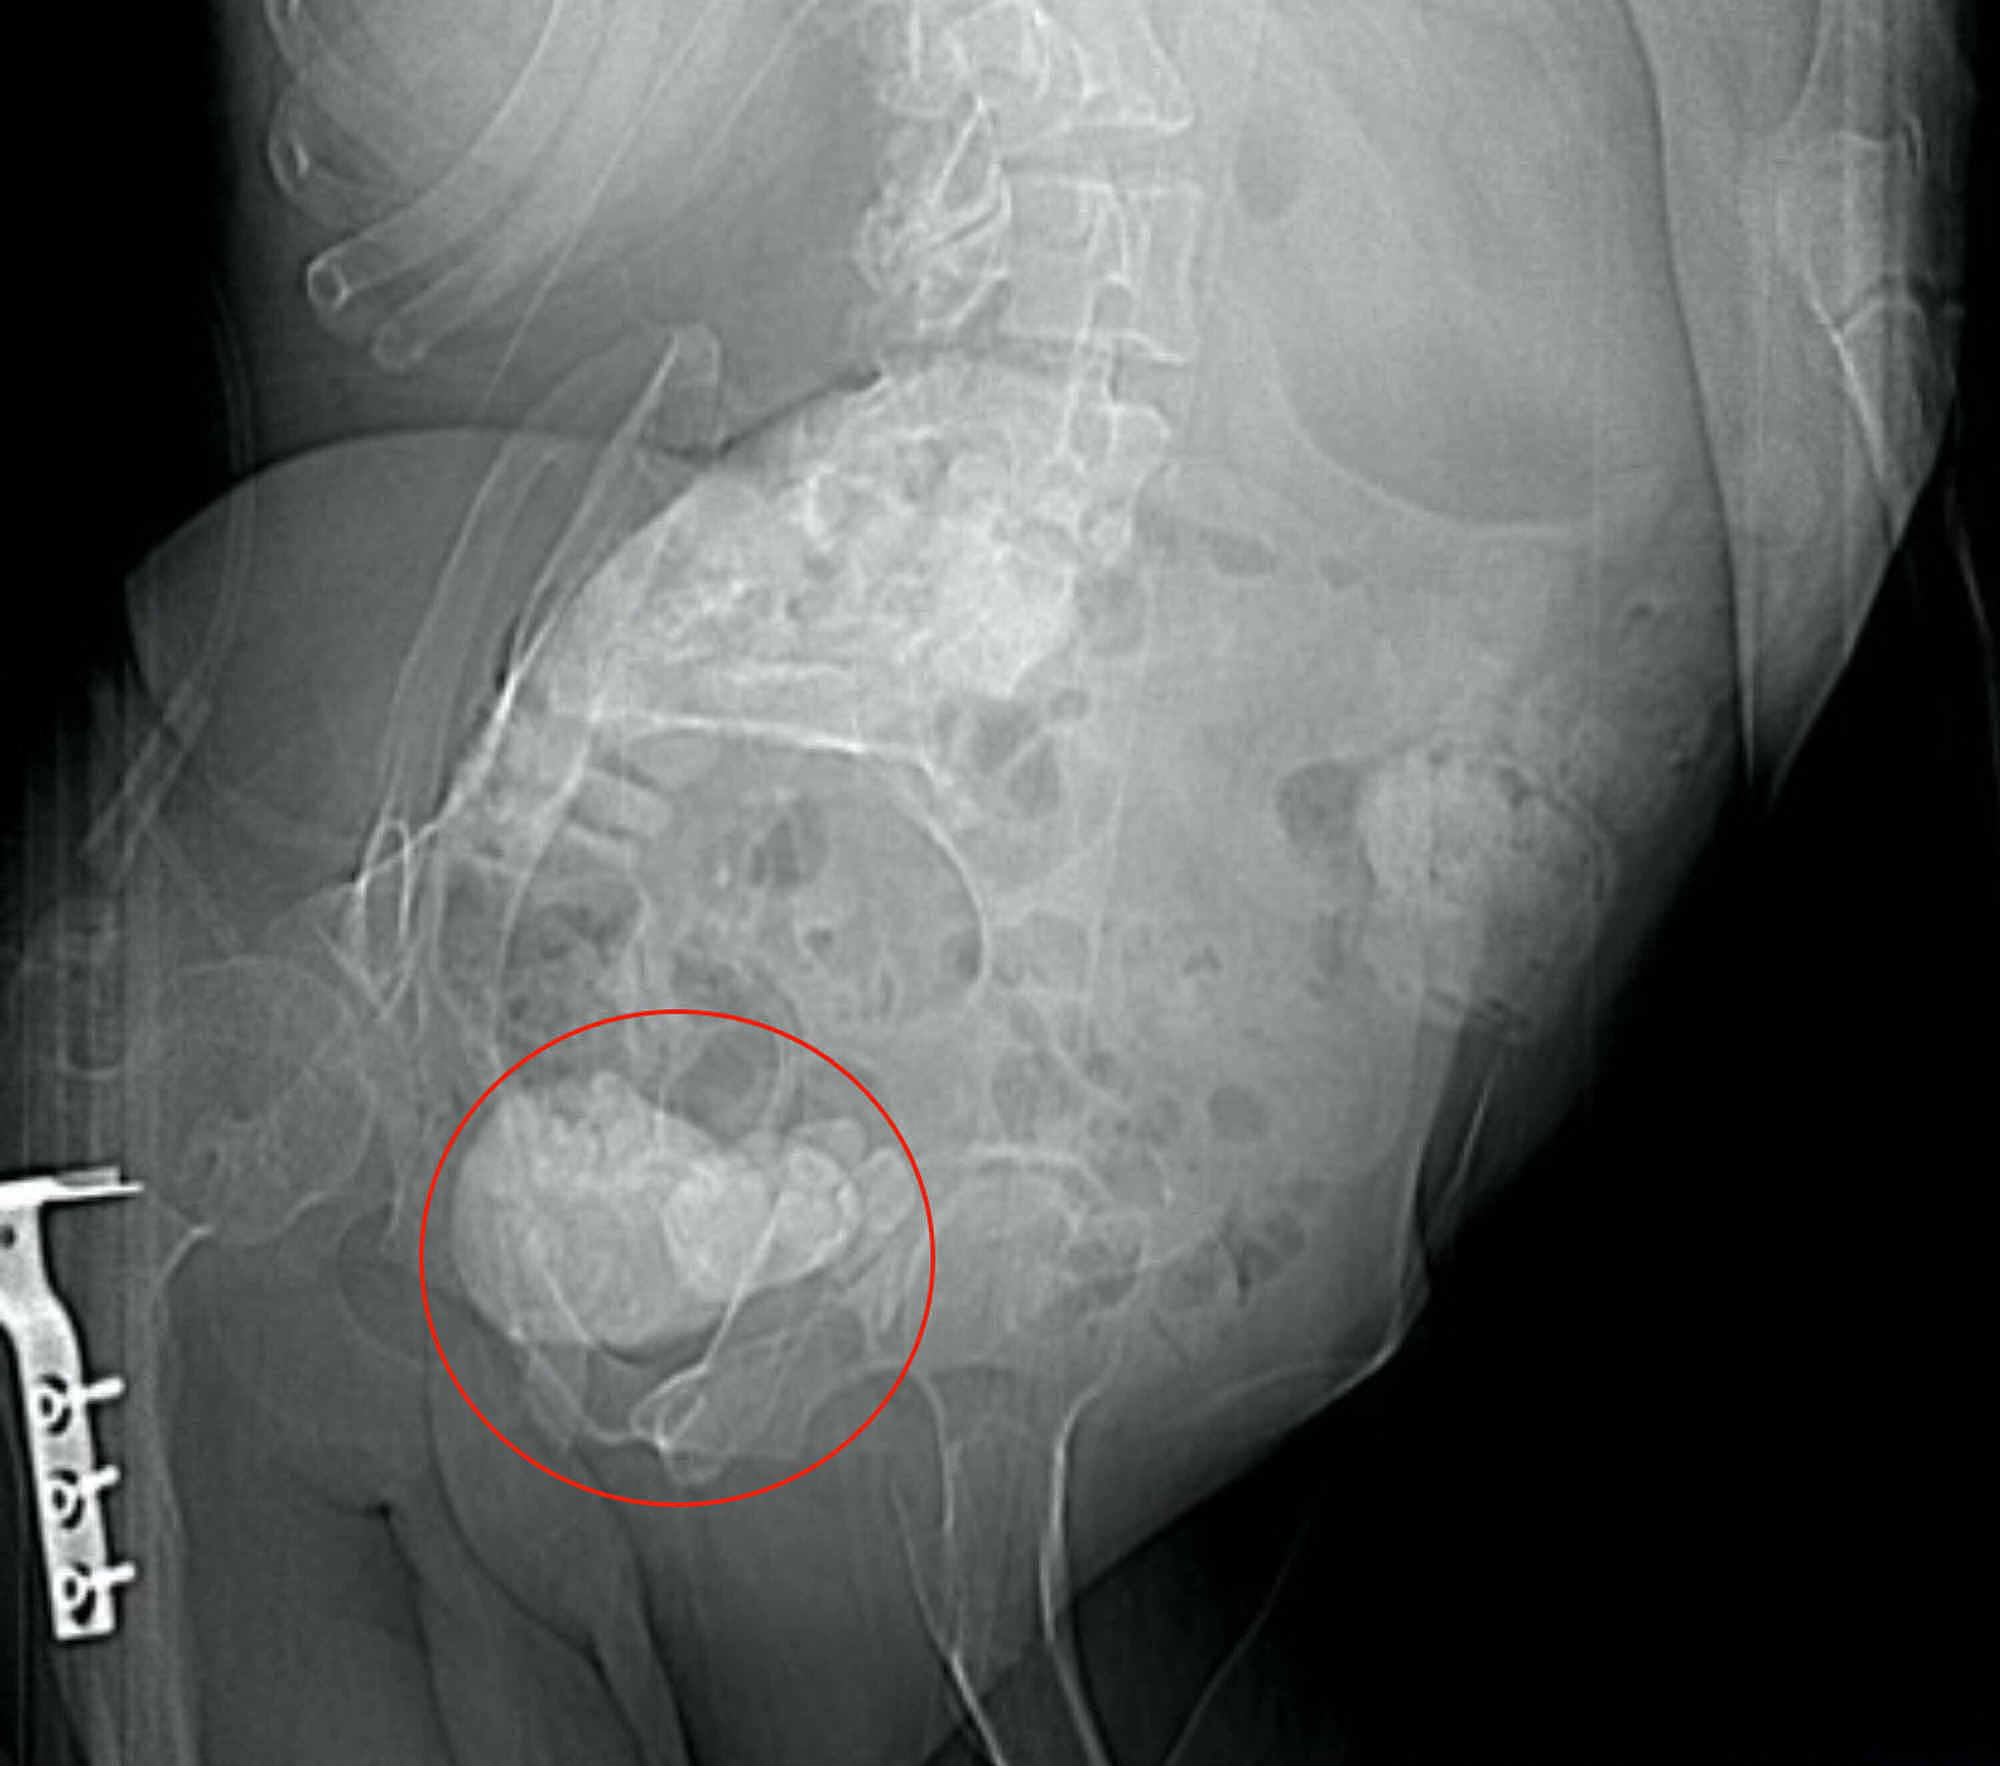

Prostatic Urethral Calculus What Causes Calcium Deposits In Prostate Treatment is usually unnecessary if there are no symptoms, but for those experiencing pain or. A diet high in calcium doesn’t cause calcification. Calcium deposits may also occur in areas with injury, infection, or cancer. In older men, benign prostatic. Since hypoparathyroid patients on calcium supplementation are known to be at risk for urinary tract stones if their calcium goes. What Causes Calcium Deposits In Prostate.

Cureus Total Osseous Calcification of the Prostate Gland What Causes Calcium Deposits In Prostate Prostatic calcifications are most often an incidental and asymptomatic finding, but they have been associated with symptoms. Prostatic calcification is usually associated with prostatic inflammation, and there are a cause and effect relationship between. Treatment is usually unnecessary if there are no symptoms, but for those experiencing pain or. A diet high in calcium doesn’t cause calcification. Since hypoparathyroid patients. What Causes Calcium Deposits In Prostate.